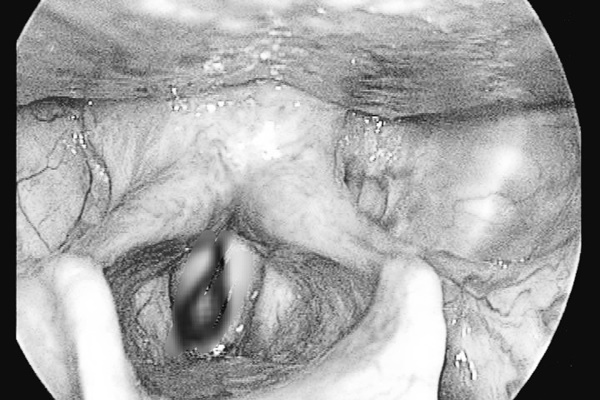

Con đỉa to bằng đầu đũa, dài khoảng 5cm được gắp ra từ mũi của bệnh nhân (Ảnh: BV).

Vì thế, các bác sĩ tiến hành gắp dị vật sống cho bệnh nhân bằng phương pháp nội soi mũi. Dị vật được lấy ra là con đỉa còn sống dài khoảng 5cm, to bằng đầu đũa.

Đây là trường hợp bệnh nhân có dị vật sống nằm ở vị trí khá phức tạp. Đỉa chui vào khe cuốn mũi, con đỉa sống lâu ngày nên càng ngày càng to lên, hút máu khiến thành cuốn mũi của bệnh nhân bị viêm loét, gây chảy máu mũi.